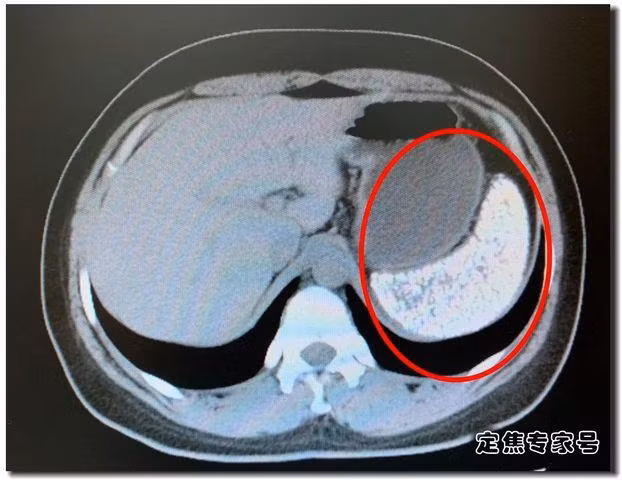

Lá lách của Hà Lệ Lệ có vô số vôi hóa.

Tất cả các bác sĩ trong phòng phẫu thuật có một chút bối rối, tự hỏi đây là gì? Sỏi hay là vôi hóa? Sau một tuần, kết quả bệnh lý được đưa ra.

Đó là một bệnh nang sán, và kháng thể IgG của nang sán trong máu là dương tính. Điều này cũng có nghĩa là Hà Lệ Lệ không chỉ bị bệnh nang sán, mà còn có kháng thể trong máu. Nang sán là gì? Nó chính là sán dây trong thịt lợn, những hạt màu trắng này là lượng lớn trứng sán phát triển đến một giai đoạn nhất định rồi ngừng lại, sau đó biến đổi thành điểm vôi hóa. Lá lách của Hà Lệ Lệ chứa vô số vôi hóa.